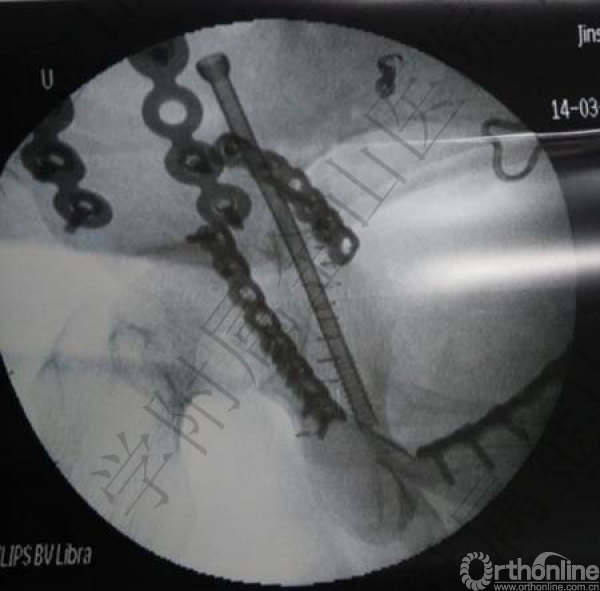

骨科:左侧骶髂关节脱位螺钉内固定术(稳定骨盆后环);

髂嵴入路+Stoppa入路

6h手术